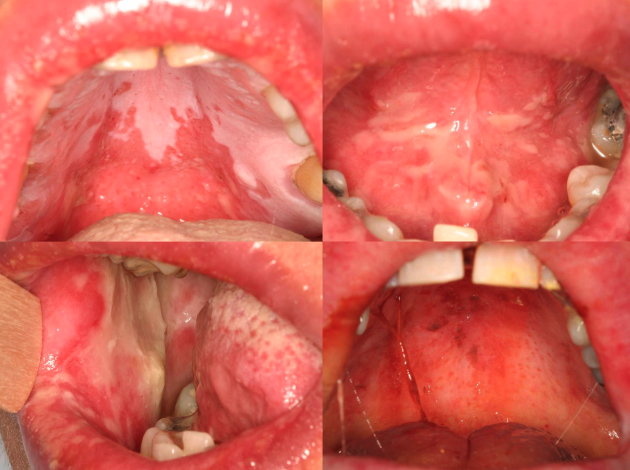

what condition?

• Often asymptomatic

• Posterior buccal mucosa

• Lacy white striations (Wickham striae)

• almost always bilateral

lichen planus reticular form

• Often symptomatic

• Striae at periphery of erythema

lichen planus Erythematous form

• Least common form

• Usually symptomatic

• Ulcers with striae and erythema

ulcerative lichen planus